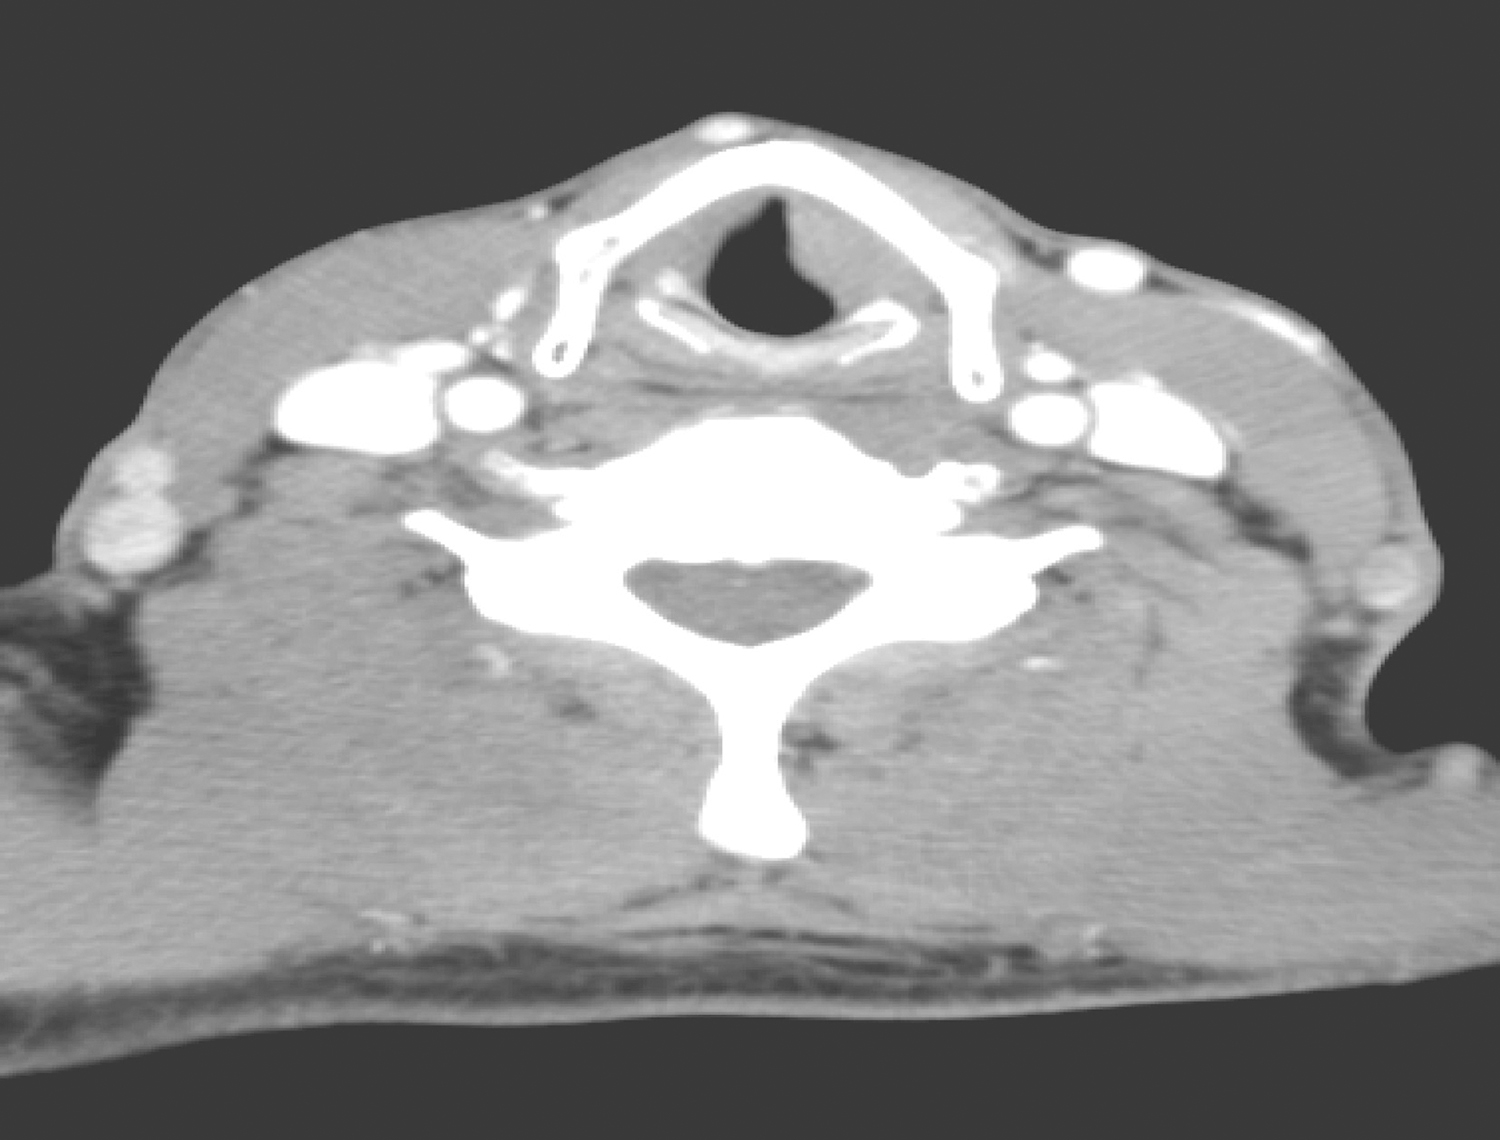

2.2015年6月12日颈胸部CT

(1)声门区左侧声带明显增厚,最厚处约0.8cm(图2),强化较明显,病变可疑侵及前联合。

图2 颈部增强CT示左侧声带明显增厚

(2)甲状腺多发低密度结节,大者约1.3cm×1.1cm,边界清楚;右侧上颌窦轻度炎症,鼻咽、口咽、下咽未见明确异常。

(3)双侧颌下、颈深链多发小淋巴结,大者短径约0.8cm。

(4)左肺上叶、右肺中上叶散在多发条索影,双肺尖胸膜增厚,余肺未见明确结节及实变。

(5)纵隔、双肺门未见明确肿大淋巴结。

(6)双侧胸腔、心包未见积液。

影像学诊断:

(1)喉癌可能性大,请结合镜检。

(2)甲状腺多发低密度结节,请结合超声检查。

(3)右侧上颌窦轻度炎症。

(4)双侧颌下、颈深链多发小淋巴结,建议随诊。

(5)左肺上叶、右肺中上叶多发条索影,双肺尖胸膜增厚,建议随诊。